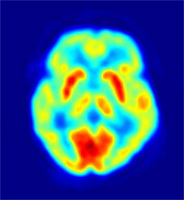

Tomografía por emisión de positrones:

| Tomografía |